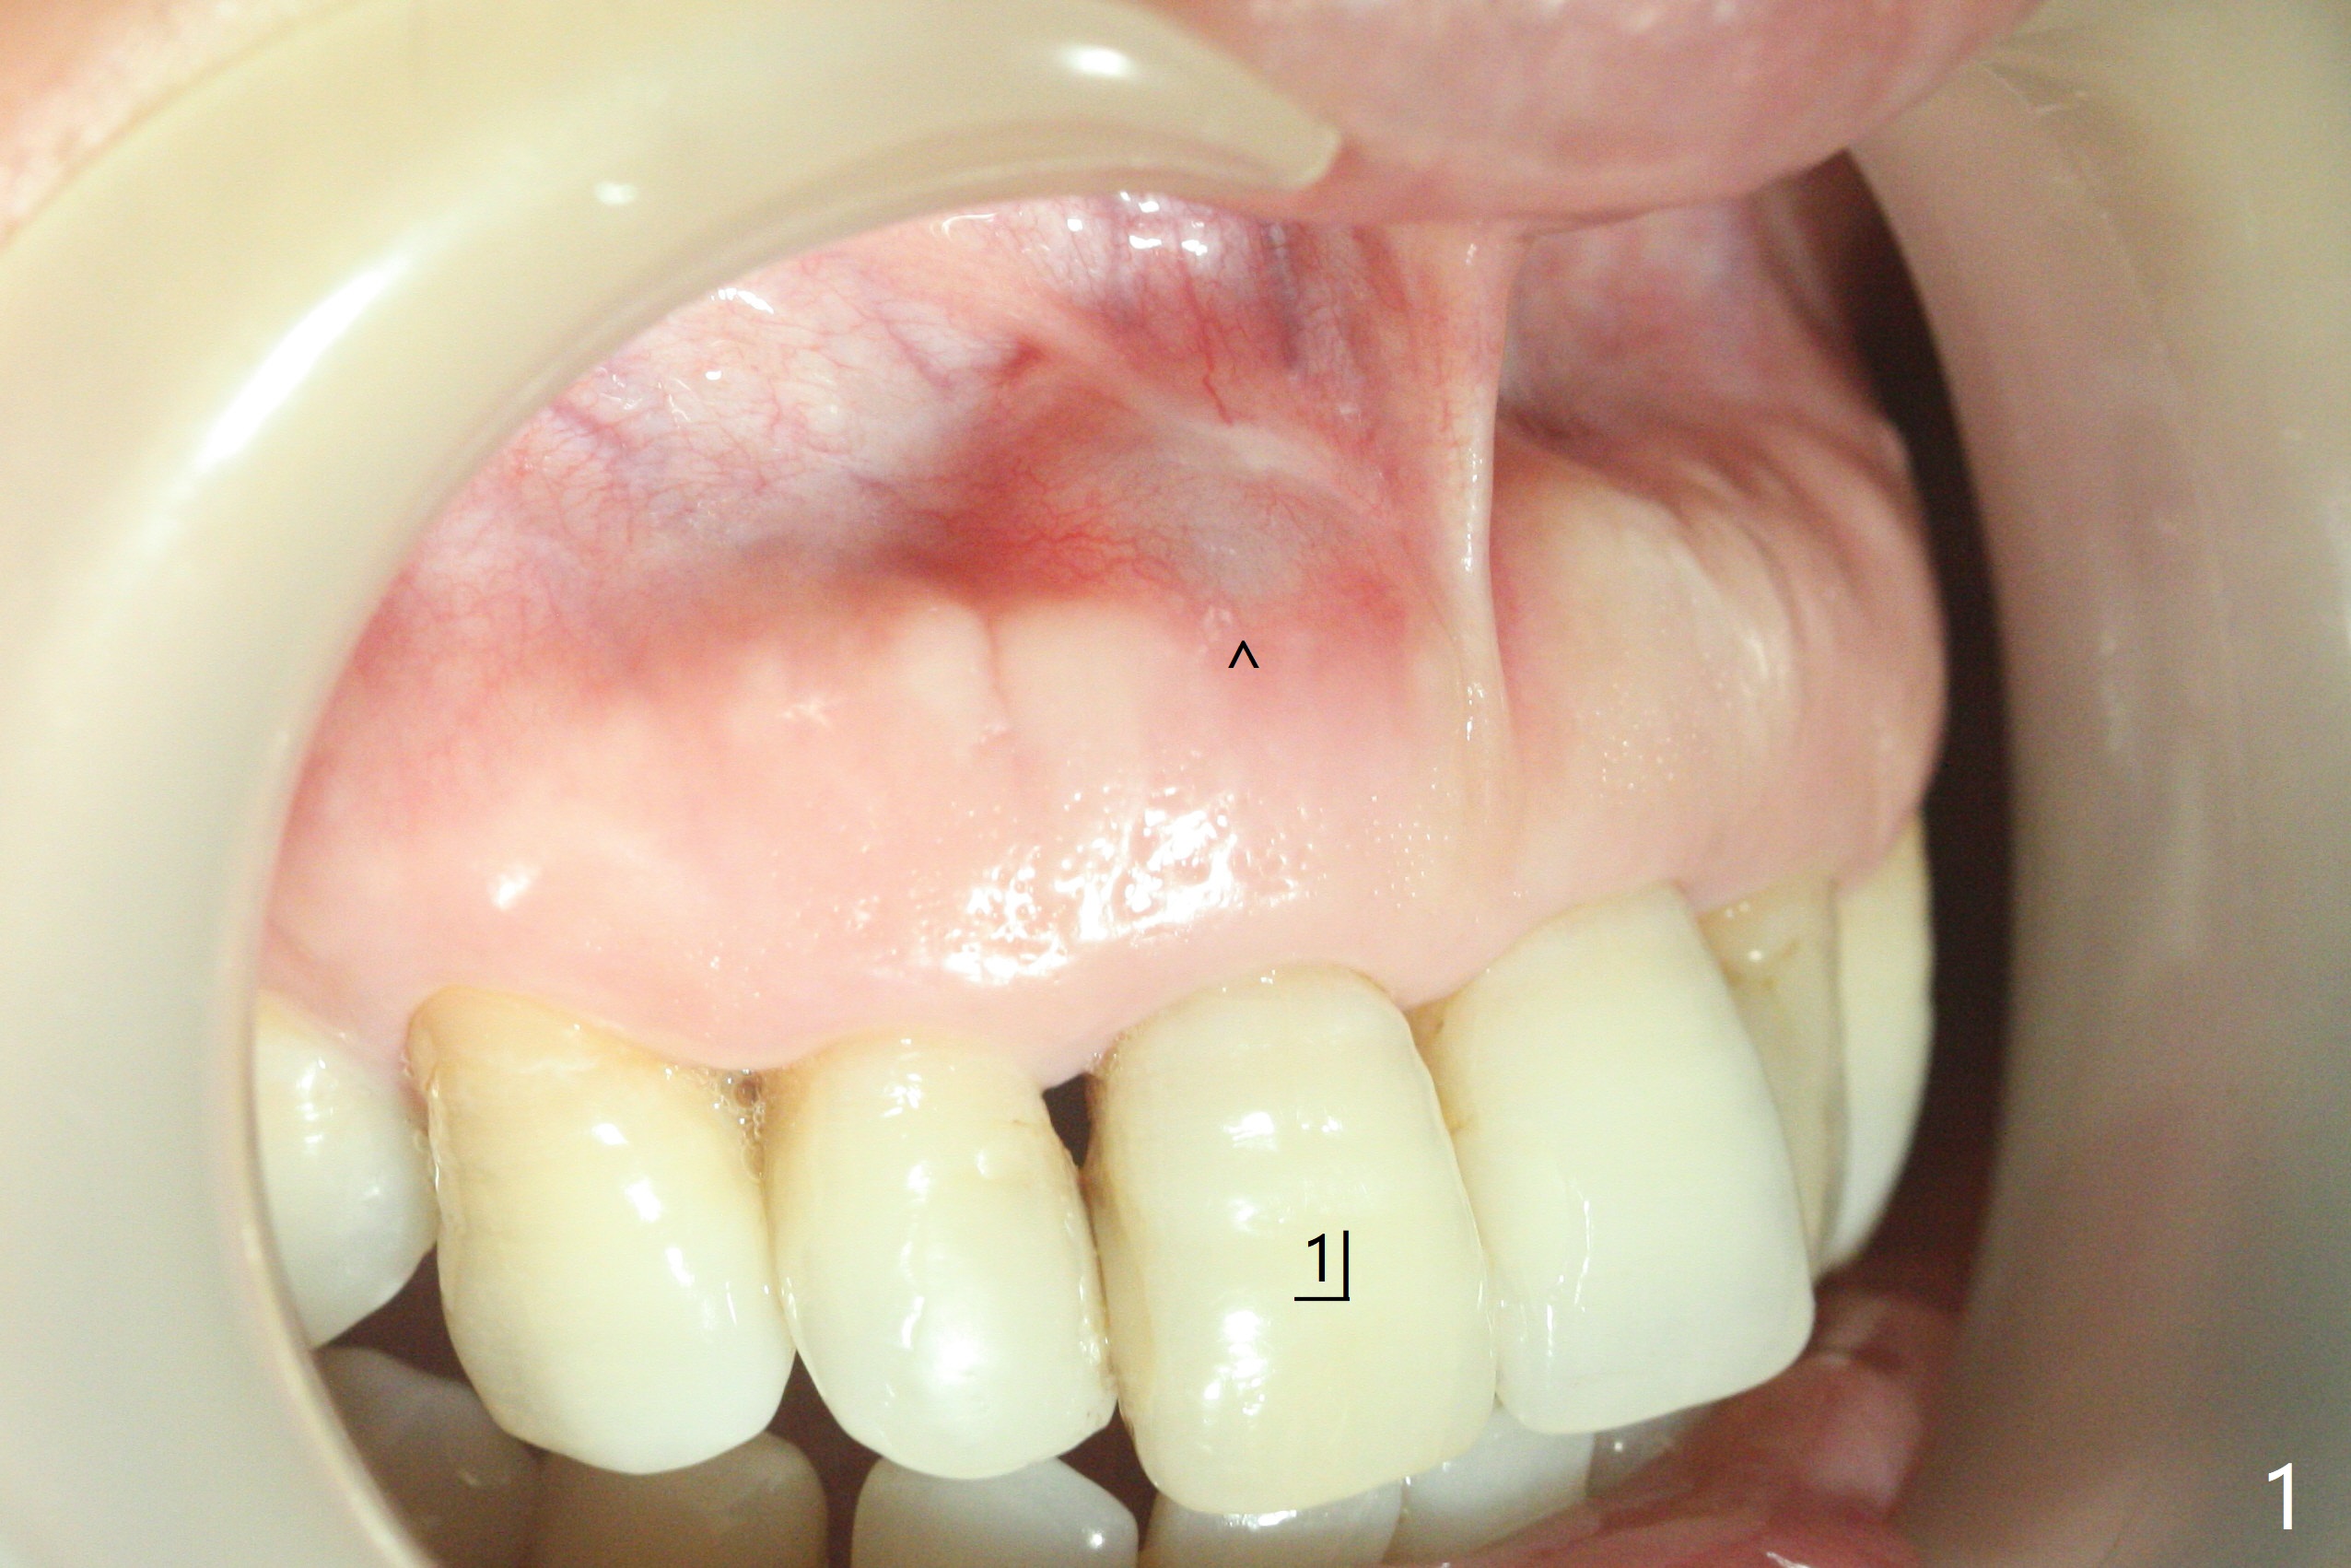

单个门牙变色往往是牙髓坏死所致,根管充填后做漂白,防止漂白泡沫跑到根尖孔之外,这种顺序可以改变吗?53岁女右上1根尖无痛性红肿(图一:^),牙冠变色(图二),牙髓测定:死髓,伴有根尖阴影(图三),中切牙需要根管治疗,什么时候漂白最好,步骤便利?根管治疗后做内漂白,必须把牙胶尖取出,釉牙骨质交界处之下,牙冠长,如这个病例,取出可能困难。我们准备尝试根管治疗当中做漂白,由于死髓牙,根管治疗可以不需要局麻,三个牙齿暴露在橡皮障之外(图四),以便术中漂白观察。根管治疗当中使用大量漂白水,好象并没有改善颜色(图五)。所以在根管口(图六)注入35%双氧水(漂白液,胶状),适当超越釉牙骨质交界处。万一双氧水气泡跑出根尖孔,我们将用生理盐水冲洗,不过这个意外没发生。双氧水也放置在患牙表面(外漂白),两次漂白后(每次20分钟),病人满意牙冠颜色改变(图七)。冲洗,擦干后,在根管中放置氢氧化钙糊剂。预约一个月后完成根管充填,如果牙冠颜色反弹,再次漂白。充填前需要多次冲洗,清除残余双氧水,后者抑制树脂固化。